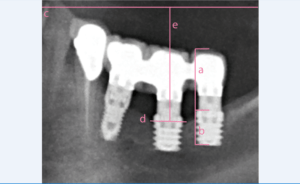

Para definir o rácio coroa-implante, o CHS e a perda óssea utilizaram-se radiografias panorâmicas calibradas através de um comprimento conhecido na radiografia tal como o do implante dentário.

O rácio coroa-implante foi determinado mediante a divisão do comprimento do implante pelo comprimento da restauração protésica colocada sobre o mesmo. A medição da altura da coroa realizou-se no eixo maior dos dentes anteriores e pré-molares e na zona média da coroa, a nível do sulco vestibular (intercuspídeo) para os molares, até à plataforma do implante. A linha de medição devia ser totalmente perpendicular à plataforma do implante formando um ângulo de 90º com a mesma. (figura 1).

O primeiro passo para medir o CHS foi traçar uma linha que representasse o plano oclusal na radiografia panorâmica. Desde um ponto de vista protésico, o plano oclusal é um plano imaginário delimitado pelas bordas incisais dos dentes anteriores mandibulares e a ponta das cúspides vestibulares dos pré-molares e molares inferiores6-9. Estes pontos foram identificados na radiografia panorâmica e traçou-se uma linha unindo-os. O segundo passo foi traçar uma linha reta que unisse o ponto mais alto da crista óssea em mesial e distal de cada um dos implantes incluídos no estudo. Finalmente, traçou-se uma linha perpendicular ao plano oclusal partindo do centro da linha da crista óssea; a medida linear obtida entre estes dois pontos foi o valor utilizado para o CHS6,7. (figura 1)